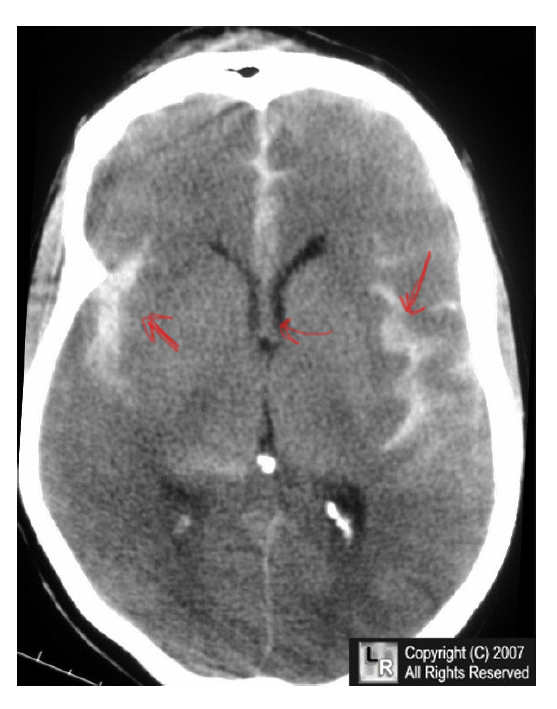

• If there is an aneurysm in a cerebral artery in the subarachnoid space, it can result in a subarachnoid hematoma. Blood will flow into the sulci of the brain and in the cerebrospinal fluid. Symptoms include:

• thunderclap headache

• nausea, vomiting, LOC

• neck stiffness

• visual changes

• Label the type of hematoma

A) subarachnoid hematoma